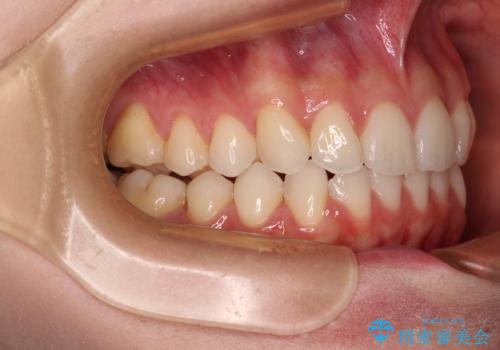

前歯のデコボコと深い咬み合わせ インビザラインできれいに改善

- 前歯のデコボコと下の前歯が隠れてしまう咬み合わせを気にして来院された患者様です。

インビザラインによる上下歯列の拡大と、IPR(歯と歯の間を削る)にるスペースの獲得により、口元のデコボコとディープバイトを改善することとしました。